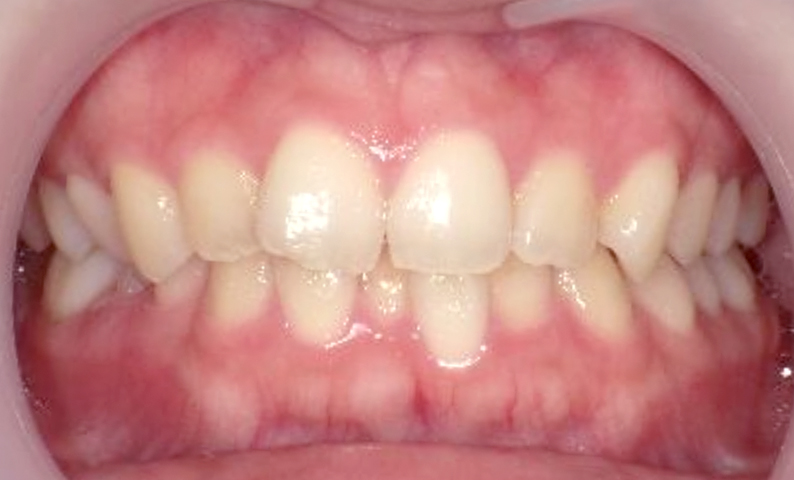

症例_004 上下顎の部分矯正

治療期間:8ヶ月金額:54万円+税女性前歯のガタガタ捻転歯

| Before | After |